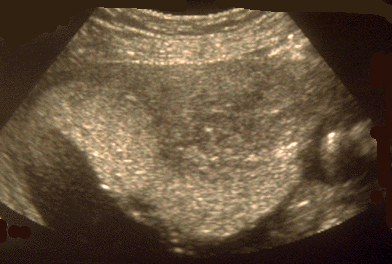

Utérus gravide ; myome antérieur, sous le placenta.